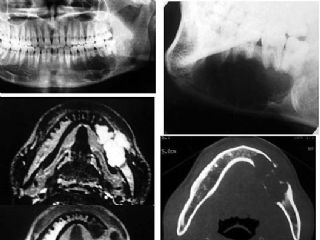

颌骨骨肉瘤影像学图片

成釉细胞瘤影像学图片

残留牙根囊肿影像学图

鼻腭囊肿影像图片

下颌骨骨折X光片

牙槽突骨折X线图片